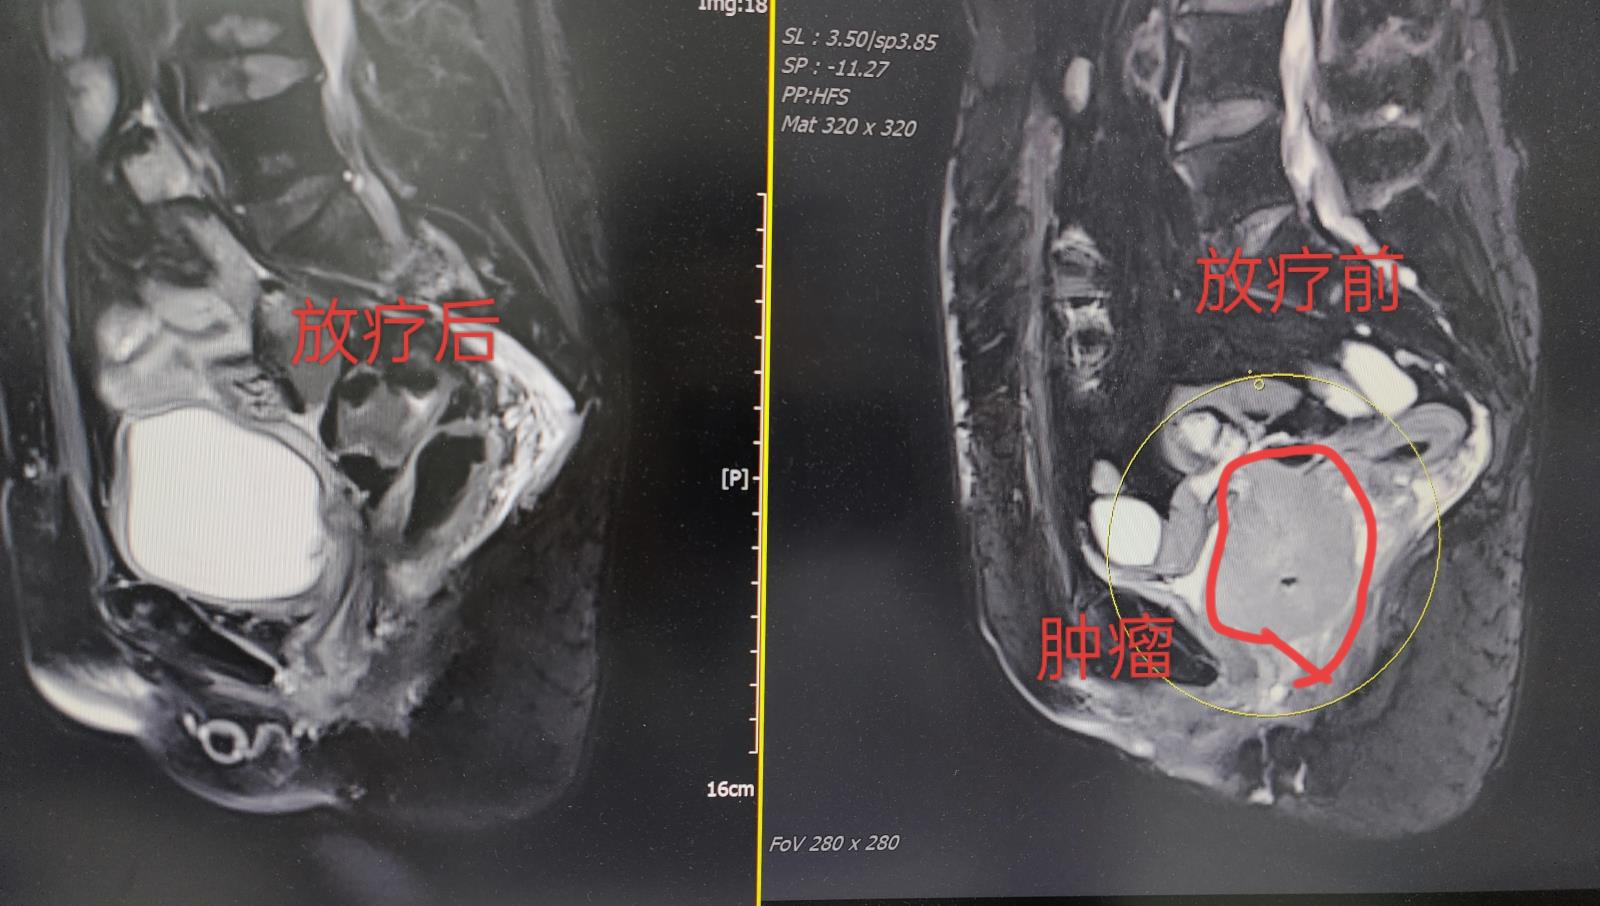

70多岁的王婆婆,1年前于院外行宫颈癌手术,术后病理提示:低分化鳞状细胞癌伴盆腔淋巴结转移,由于各种原因她放弃了选择术后进一步的放射治疗和化学治疗。不幸的是,术后短短半年时间她出现了外阴疼痛不适等症状,复查结果提示:宫颈癌术后复发,肿瘤广泛侵犯直肠、膀胱,此刻的她仍然将化学治疗“拒之门外”,伴随肿瘤复发引起的一系列症状让她生活质量大大下降。

2023年10月,在家人的陪同下抱着将信将疑的态度她来到肿瘤科就诊,经过主治医师对婆婆进行全面评估,并与病人、家属充分沟通各种治疗方案,最终他们选择了在我科进行精准放射治疗以控制肿瘤。方案选择确定后,主管医生按精准放射治疗标准流程为王婆婆及时完成了模拟放疗体位固定、影像学定位,紧接着确定了照射靶区及勾画正常组织与器官,并给出了处方剂量与正常器官限制剂量,由肿瘤科高级医师审核后,物理师按照临床医师的要求利用专业的系统设计射野及布野,物理师与主管医生反复讨论评估,最终为王婆婆确定最优的放疗计划。

2023年10月—2023年12月,王婆婆在家属与肿瘤科医护团队的精心照护下顺利完成了放射治疗,症状得以缓解,生活质量大大改善,病人家属都表示异常感激、选择了相信肿瘤科的医护团队。在最近的复查中提示病灶接近完全缓解,当然,为帮助王婆婆更好的控制、让生活质量再提升,肿瘤科医疗团队也在尽心尽力地与病人、家属沟通全身治疗的方案。